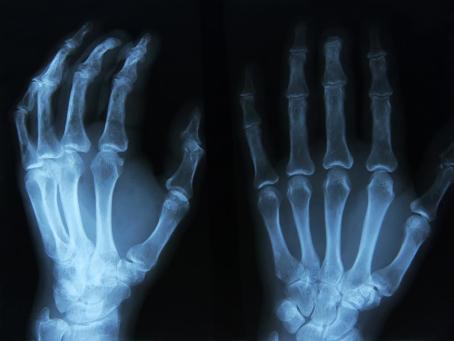

Not much was known about the composition of an atom until Wilhelm Conrad Roentgen (1845—1923) discovered in 1895, while experimenting with a gas discharge lamp, a strange radiation that could penetrate solid matter. He named it the “X-ray”, and an astonishing (for the time) X-ray image of his wife’s hand circled the world. A year later, Henri Becquerel (1852—1908) experimented with phosphorescence.

X-ray image of a patient’s left hand. The oldest image in the history of medical diagnostics is the 2D image of a hand’s interior structure.